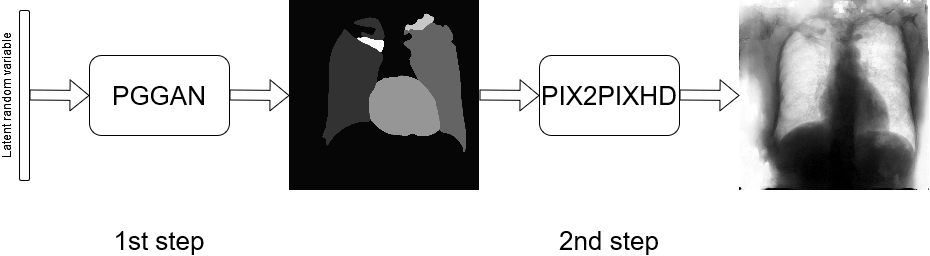

In this approach, the generation procedure is divided into two steps. The first one consists in generating the labels through a PGGAN, while, in the second, the translation from the label to the corresponding chest X–ray image is carried out, using Pix2PixHD (see Figure 2).